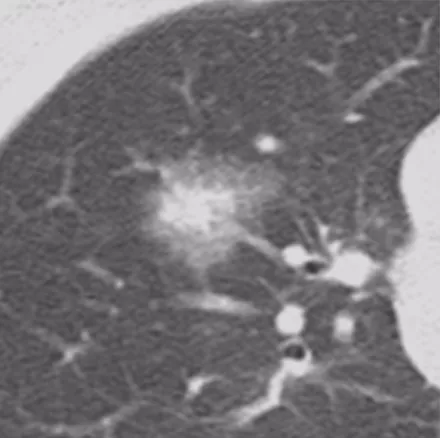

微浸润性腺癌(MIA)

进一步发展里面出现实性成分,或者结节的大小逐渐增大。微浸润性腺癌多位于肺外周,多为单发,一般<2cm,一般到了2cm就更严重了。最主要的是影像学多表现为边界清楚的部分实性结节,GGO比例>50%,实性成分多≤5mm。组织学上肿瘤细胞贴壁生长为主,多为非粘液型。此时要考虑微浸润的问题,这个时候手术效果还是非常好的。

浸润性腺癌(IA)

病灶较前几种类型更大,多为实性或以实性成分为主(>5mm,GGO比例<50%)的结节,形状多为不规则,边界较清楚,开始出现一些明显的肿瘤征象,可有分叶、毛刺、棘突、空泡征、支气管充气征、血管集束征、胸膜牵拉征等。临床医生判断这些征象没有什么问题,但是这个时候对于呼吸医生来说,应该在这之前给病人一个比较合理的判断。